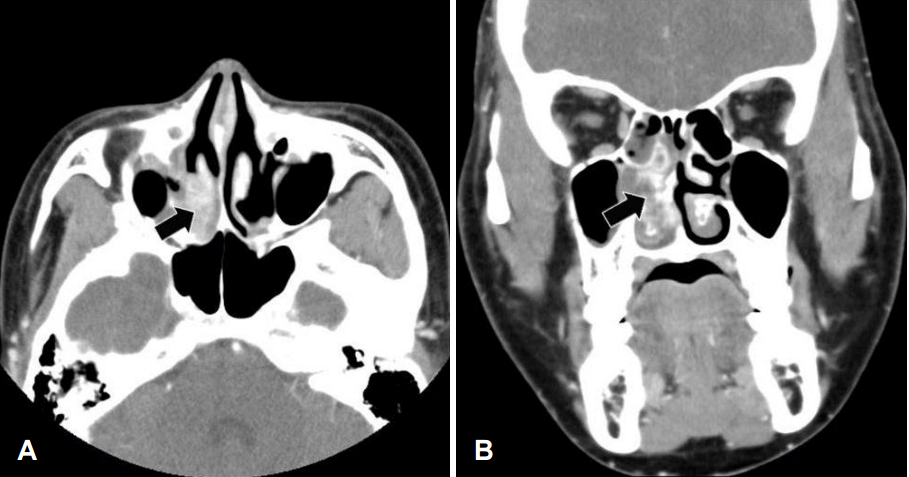

Fig. 1.

Nasal endoscopy shows a hypervascularized irregular mass (black arrow) occupying the right nasal cavity. The mass originated from the posterior section of the right inferior turbinate. S: septum, I: inferior turbinate, M: middle turbinate.